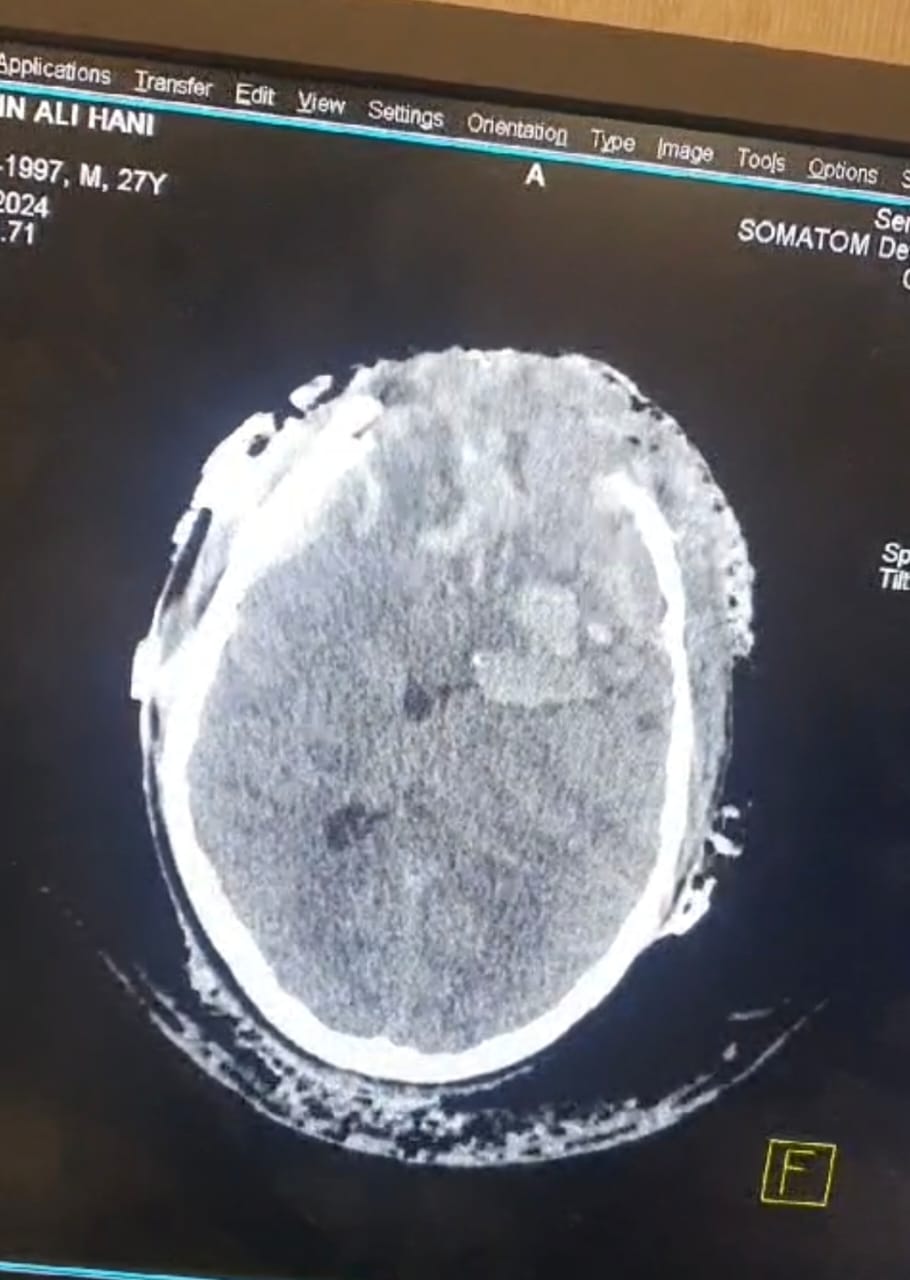

ذكر اخصائي جراحة الدماغ والعمود الفقري الدكتور مصطفى الحيدري بأن مريض شاب يبلغ من العمر (20) عام من أهالي السماوه تمت احالته من مستشفى الإمام الحسين في محافظة المثنى إلى مدينة الصدر الطبية في النجف كان قد تعرض لشدة خارجية على الرأس ادت إلى حدوث(نزف شديد و تهشم في عظم الجمجمه مع تمزق وتهتك الاغشيه السحائيه وأنسجة الدماغ وخروجها خارج الرأس).

مبيناً ” ان الحالة تطلبت إجراء تداخل جراحي طارئ استمر مايقارب (6) ساعات تم خلاله رفع جزء من عظم الجمجمه المتضرر و إزالة أنسجة الدماغ التالفة وترميم الاغشية السحائية وايقاف النزيف وغلق وهندمة الجرح.